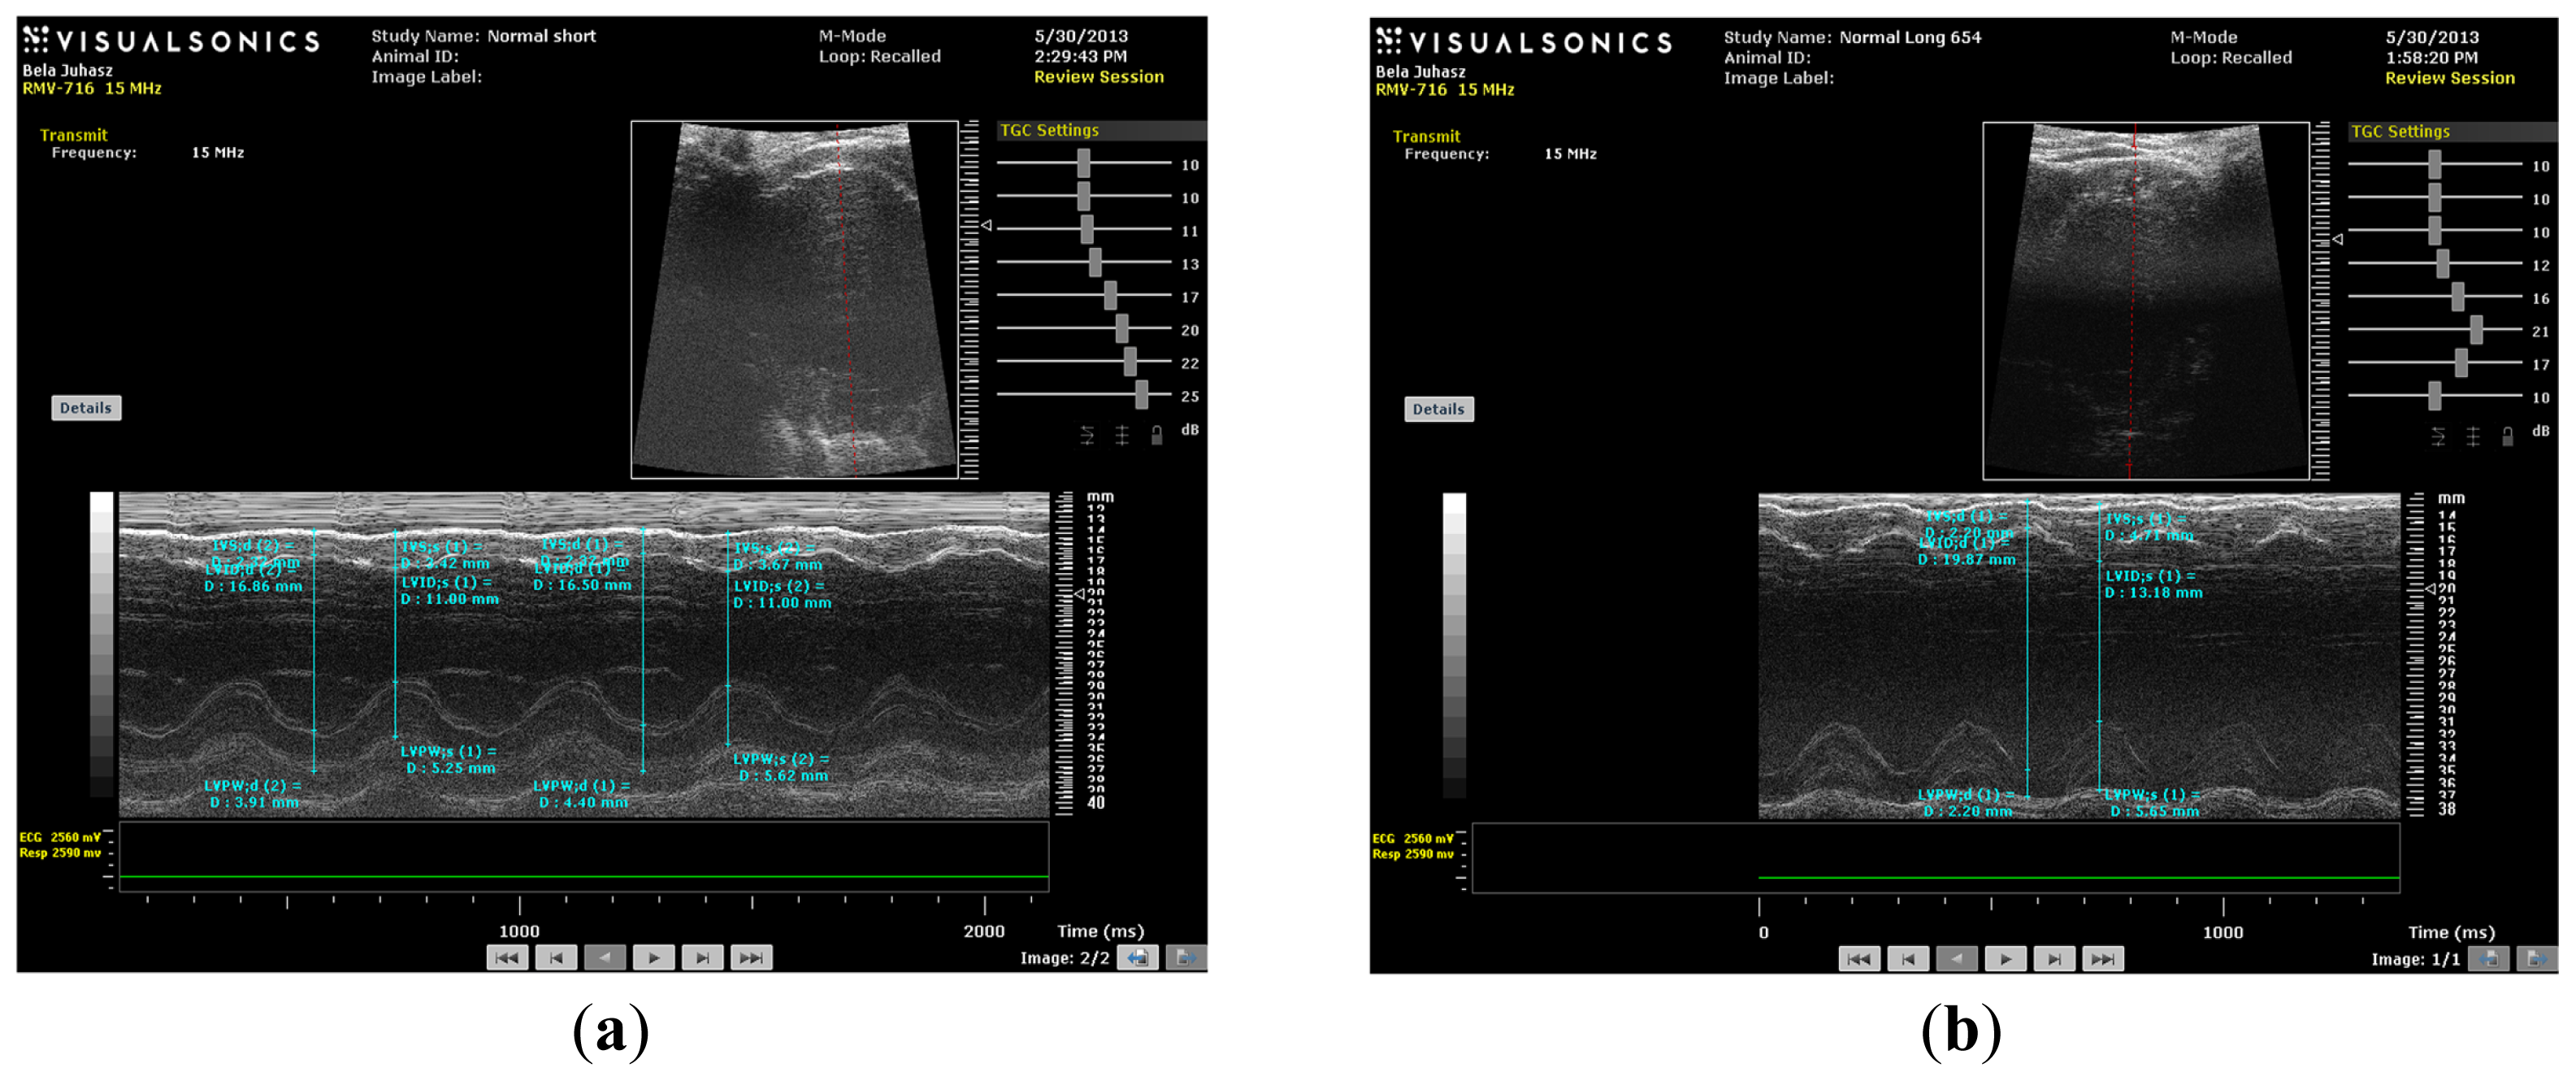

(a) M-mode image of control short (CS) heart; (b) M-mode image of control long (CL) heart; (c) M-mode image of HC short (HCS) heart; (d) M-mode image of HC long (HCL) heart.

M-mode images demonstrate cross-sections of the heart swept by the instrumentation over a defined time period. This evaluation is conducted by placing the cursor line on 2D images at the mid-ventricular level, with the largest diameter in either the parasternal long or parasternal short axis view (on the M-mode pictures at the upper part 2D views with the cursor; at the lower part, the tracing at the cursor line could be seen). This technique, which provides a very high temporal resolution, allows the end systolic [minimal diameters, left ventricular internal diameter at end-systole (LVIDs)] and end diastolic [maximal diameter, left ventricular internal diameter at end-diastole (LVIDd)] diameters to be precisely measured. These parameters are used to calculate fractional shortening [(LVIDd − LVIDs)/LVIDd] and ejection fraction [(LVIDd − LVIDs)2/LVIDd2] (cubed formula), which are indicators of left ventricular emptying capacity. Normally, the heart ejects more than 50% of its end diastolic volume (ejection fraction), and the diameter shortens more than 25% (linear ejection fraction or fractional shortening). When the myocardial tissue is damaged (typically by oxidative stress), its contractile function is attenuated and emptying capability decreased.

As shown in Figures 4 and 5, the values of fractional shortening (FS) and ejection fraction (EF) of the left ventricle were significantly reduced in HC long animals relative to their values in non-hypercholesterolemia control rabbits (p < 0.05) and to animals maintained for shorter time periods on hypercholesterolemia-inducing chow (HC short) (p < 0.05). These outcomes are expected based on previous studies, which reveal significant positive correlation between the occurrence of cardiac insufficiency and associated heart failure with possible left ventricular hypertrophy [22–24]. The aforementioned echocardiographic data provides insight into the influence of high cholesterol on the underlying pathogenesis of cardiovascular disease and helps account for other observations described in the present report, such as increased infarct magnitude in hypercholesterolemia animals. No significant differences in Groups I–III were observed. This expectation shows that neither ageing itself nor short-term hypercholesterolemia afflict the systolic and diastolic parameters and normal heart function. Although, in animals receiving a long-term cholesterol diet, these values were significantly lower (p < 0.05), which shows that long-term hypercholesterolemia can deteriorate left ventricle systolic function. As seen in Table 1, no significant differences in other echocardiographic parameters were measured. It should be also noted that the left ventricle (LV) masses of Groups II and IV were higher than the LV masses of the short-treated animals, although this only represents that the LV mass is correlated with increasing body weight, since these animals were five months older at the moment of extermination.